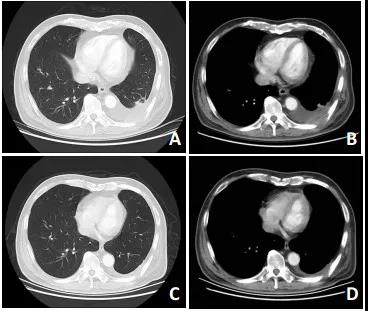

至2019年2月26日复查,肿瘤继续缩小(较基线缩小23%),无新增病灶,总体评效为缩小的SD(图 1)。用药期间患者间断恶心1级,并出现双上肢和双下肢水肿1级(图 2)。下肢水肿原因在排除心源性水肿、肾源性水肿、下肢静脉血栓和营养不良等因素后,考虑为沃利替尼导致的外周水肿。给予利尿消肿药物治疗后水肿有所好转,但停药后反复。综合考虑患者不良反应较轻,未调整用药。

A,B:沃利替尼治疗前(2018年5月2日);C,D:沃利替尼治疗后(2019年2月26日)

图 1 胸部CT检查